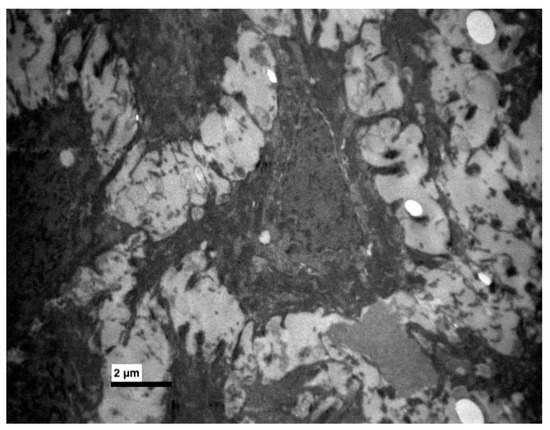

Transmission Electron Microscopy (TEM)

3. Results